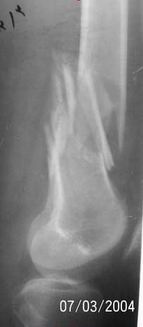

A 34 year old male was injured in a car accident.

The femur injury was treated by long retrograde interlocking nail.

I would expect healing though alignment could have been better if Poller screw or temporary wire was used.